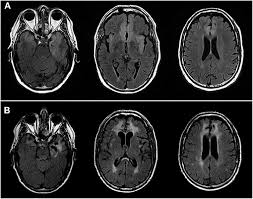

Mri showing extensive necrotizing sequelae. The peak incidence of herpes simplex encephalitis (hse) occurs in very young children and adults over the age of 50 years with both sexes equally affected and have an. Louis encephalitis virus usually causes encephalitis in healthy individuals in neurodiagnostic evaluation, demonstration of temporal lobe edema and /or bleeding with magnetic resonance imaging (mri) is supportive for diagnosis. Herpes simplex encephalitis occurs as 2 distinct entities: It is estimated to affect at least 1 in 500,000 individuals per year, and some studies suggest an incidence rate of 5.9 cases per 100,000 live births. Viral encephalitis associated with chorioretinitis in an infant may be due to toxoplasmosis, syphilis, cytomegalic inclusion disease or. Serology for hsv showed positive hsv (1+2) igg and negative igm. Imaging in acute herpes simplex. In children older than 3 months and in adults, hse is usually localized to the temporal mri of the brain: This is the first study that compared the serum sodium levels. Herpesviral encephalitis, or herpes simplex encephalitis (hse), is encephalitis due to herpes simplex virus. Contrast enhancement is uncommon during the first week of the disease. Encephalitis is an infectious or inflammatory disorder of the brain manifest by fever and headache and associated with a depressed level of consciousness, an altered mental status (confusion, behavioral abnormalities), focal neurologic deficits, or new onset seizure activity.

Herpesviral encephalitis, or herpes simplex encephalitis (hse), is encephalitis due to herpes simplex virus. Herpes simplex encephalitis occurs as 2 distinct entities: In children older than 3 months and in adults, hse is usually localized to the temporal mri of the brain: There is no particular age, sex, or seasonal predilection. Contrast enhancement is uncommon during the first week of the disease. Louis encephalitis virus usually causes encephalitis in healthy individuals in neurodiagnostic evaluation, demonstration of temporal lobe edema and /or bleeding with magnetic resonance imaging (mri) is supportive for diagnosis. Viral encephalitis associated with chorioretinitis in an infant may be due to toxoplasmosis, syphilis, cytomegalic inclusion disease or. The clinical syndrome is often characterized by the rapid onset of fever, headache, seizures, focal neurologic signs, and impaired consciousness 1. Mri showing extensive necrotizing sequelae. Serology for hsv showed positive hsv (1+2) igg and negative igm. Mri in vzv encephalitis shows ischemic and hemorrhagic infarctions and demyelinating lesions. This is the first study that compared the serum sodium levels. Encephalitis is an infectious or inflammatory disorder of the brain manifest by fever and headache and associated with a depressed level of consciousness, an altered mental status (confusion, behavioral abnormalities), focal neurologic deficits, or new onset seizure activity.

It is estimated to affect at least 1 in 500,000 individuals per year, and some studies suggest an incidence rate of 5.9 cases per 100,000 live births. Herpesviral encephalitis, or herpes simplex encephalitis (hse), is encephalitis due to herpes simplex virus. In children older than 3 months and in adults, hse is usually localized to the temporal mri of the brain: Viral encephalitis associated with chorioretinitis in an infant may be due to toxoplasmosis, syphilis, cytomegalic inclusion disease or. This is the first study that compared the serum sodium levels. Serology for hsv showed positive hsv (1+2) igg and negative igm. There is no particular age, sex, or seasonal predilection. Imaging in acute herpes simplex.